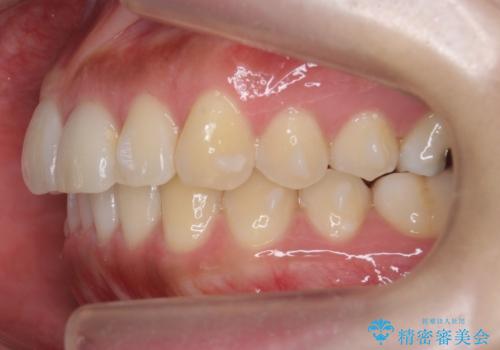

- 前歯のがたつきを主訴に来院。

前歯は目立つのでワイヤー矯正は絶対にしたくないとのことでした。

右上の奥歯を後ろに送り、前歯が出っ歯にならないように並べました。

また、右下の奥歯に一部目立たないように部分的なワイヤー矯正を行い、右下の奥歯が反対咬合になっていたのもしっかり中に入れて治療しています。

奥歯の反対咬合を治すのはインビザラインではかなり難しいのですが、しっかり治療できました。